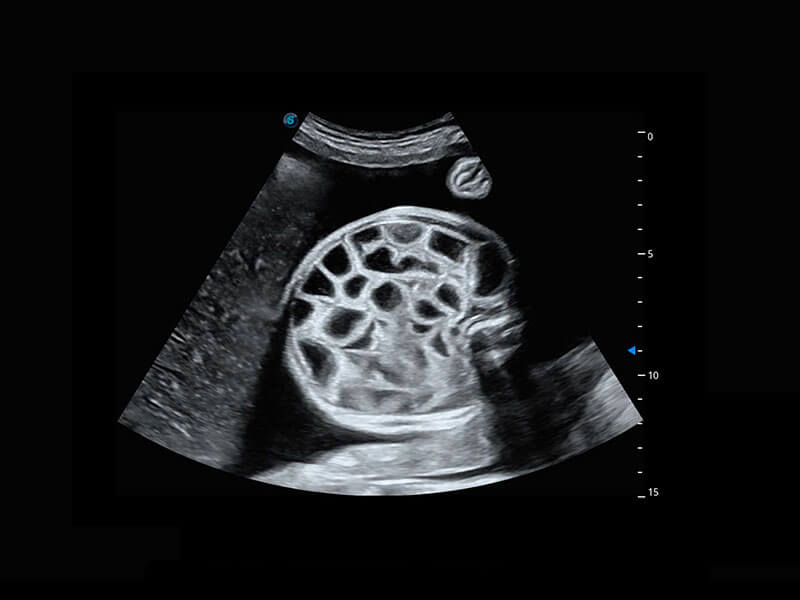

P60优异的图像质量搭载专科探头,在妇科基础疾病的诊断、卵泡生长的监测、输卵管通畅情况的判别等方面为您提供生殖应用方案。

腔内妇科-卵巢